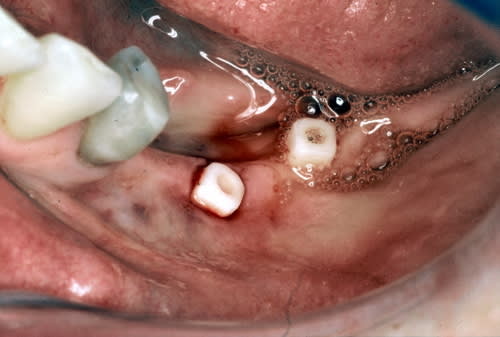

Tiens j'ai trouvé une formation sur youtube:)

question aux pro,c'est normal que le moignon soit si court,ou c'est un stade intermédiaire?( je sais qu'il va y avoir une couronne dessus:),mais il est vraiment court!

le seul truc qui ne me choque pas annie, c'est la hauteur du moignon, car, avec un usinage, l' adaptation est telle que ça n' est pas du tout génant comme sur des quenottes, en plus, ici, ça finie type cone morse vue le petit coup de maillet....enfin, j' imagine.....